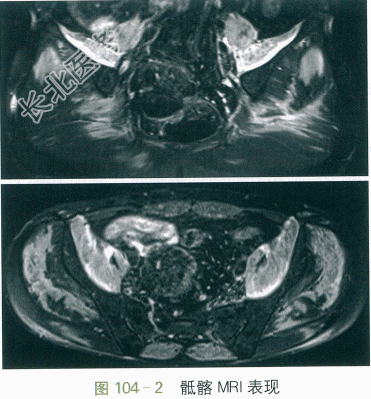

患者2012年9月起无明显诱因出现活动后气促,平地行走500米或爬三层楼即感胸闷、气促,休息后可缓解。伴轻度咳嗽,无发热、咳痰、胸痛、咯血、夜间阵发性呼吸困难、下肢水肿等。上述症状进行性加重,患者未予重视及诊治。2013年8月初无明显诱因相继出现颜面部皮疹(前额、眶周、面颊、口鼻周围紫红色充血性斑丘疹),双上肢近端桡侧、左侧颈项部、双侧大腿内侧皮疹,均为紫红色充血性皮疹,范围渐增大,伴瘙痒,无关节摩擦部位皮疹及技工手改变。2013年8月中旬开始出现四肢近端乏力,双手上举、穿裤较前困难,蹲起可,无肌痛、肢体麻木。同时出现下腰及双臀疼痛,伴晨僵,活动后可缓解。上述症状进行性加重,否认发热、四肢关节痛、光过敏、口腔溃疡、口眼干、雷诺现象等不适。遂于外院就诊,查血常规、尿常规、肝炎病毒抗体阴性,肝功能:ALT/AST77/174(IU/L),ALP/GGT103/93(IU/L),TG/TC3.21/6.37(mmol/L),X光片示双侧骶髂关节轻度炎症。予保肝、调脂、塞来昔布抗炎止痛、炉甘石和派瑞松外涂等治疗2周,上述症状无缓解,且出现轻度吞咽困难。遂至我院门诊,查ESR23mm/h,hsCRP10.7mg/L,RF、ASO(-),HLA-B27(+)。行PET-CT:双侧臀部皮下糖代谢增高的增厚软组织影(最大SUV2.9),全身肌肉多发对称性糖代谢轻度增高(最大SUV2.5),考虑为炎性改变(见图104-1)。现为进一步诊治收住病房。起病来精神睡眠可,食纳可,二便无殊,近1年体重增加约10kg。

血常规、尿常规、凝血功能(-);24h尿蛋白定量0.42g;肝肾功能:A/G38/25(g/L),ALT/AST 147/410(IU/L),ALP/GGT73/35(IU/L),Scr76μmol/L;CK16461IU/L,CK-MB367IU/L,CK-MM16094IU/L;TC/TG5.29/1.97(mmol/L);ESR35mm/h,hsCRP8.3mg/L,RF<7IU/ml;SCC4.8ng/ml,NSE28.0ng/ml,CA15-325.4IU/ml。动脉血气分析:pH7.44,PO275mmHg,PCO234mmHg,SBE2.8。自身抗体:ANA颗粒1:1000(+),抗ds-DNA抗体10.0IU/ml,抗核小体抗体2.0RU/ml,抗JO-1抗体(+),余抗ENA谱(-),自身免疫性肝炎相关抗体均(-),ANCA(-)。肺部HRCT:双下肺间质性炎症伴少许间质纤维化。心超:左房增大,肺动脉压力30mmHg,LVEF70%。骶髂关节MRI:双侧髂腰肌、腹直肌、竖脊肌及臀部肌群弥漫性异常信号,考虑肌炎表现(见图104-2)。肌电图:四肢肌肉肌源性损害。